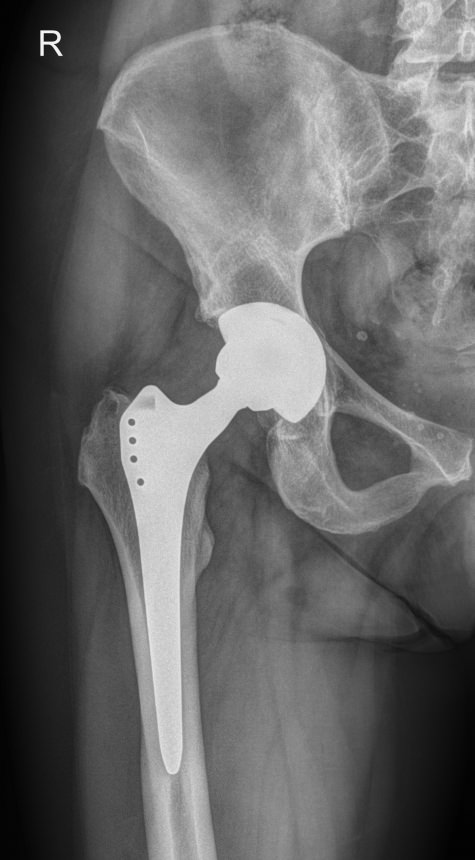

Рентгенография ― один из наиболее информативных методов диагностики патологий тазобедренных суставов. Это доступная, распространенная и неинвазивная диагностика, несущая минимальное количество ионизирующего излучения. В результате исследования можно обнаружить изменения, как травматические, так и воспалительного характера, происходящие с самыми крупными сочленениями костей в организме человека.

• Состояние суставных щелей, их симметричность и особенности;

• Соответствие вертлужных впадин головкам бедренных костей;

• Структуру костной ткани и патологические изменения в ней в области суставов;

• Ядра окостенения у детей;

• Врожденные аномалии, например, дисплазию;

• Переломы и вывихи;

• Новообразования.